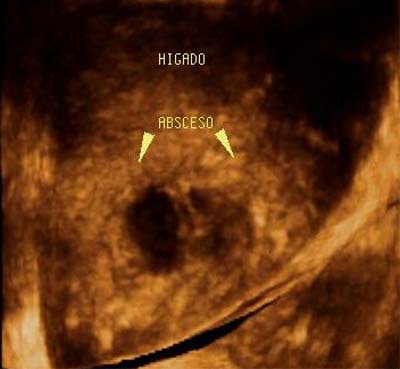

Planar imaging showed the existence of multiple very superficial liver abscesses, evidence of acute cholioangitis, and the development of chronic pancreatitis aggravated by the consumption of alcohol.

![]() |

| Figure 6a. Volumetric reconstruction using a surface-rendering technique enabled clear visualization of the complete dilated intrahepatic hepatic biliary tree, which demonstrated irregular contours and contained thick material. |

| Figure 6b. Volumetric reconstruction with a surface-rendering technique shows one of the superficial abscesses seen in this patient. |